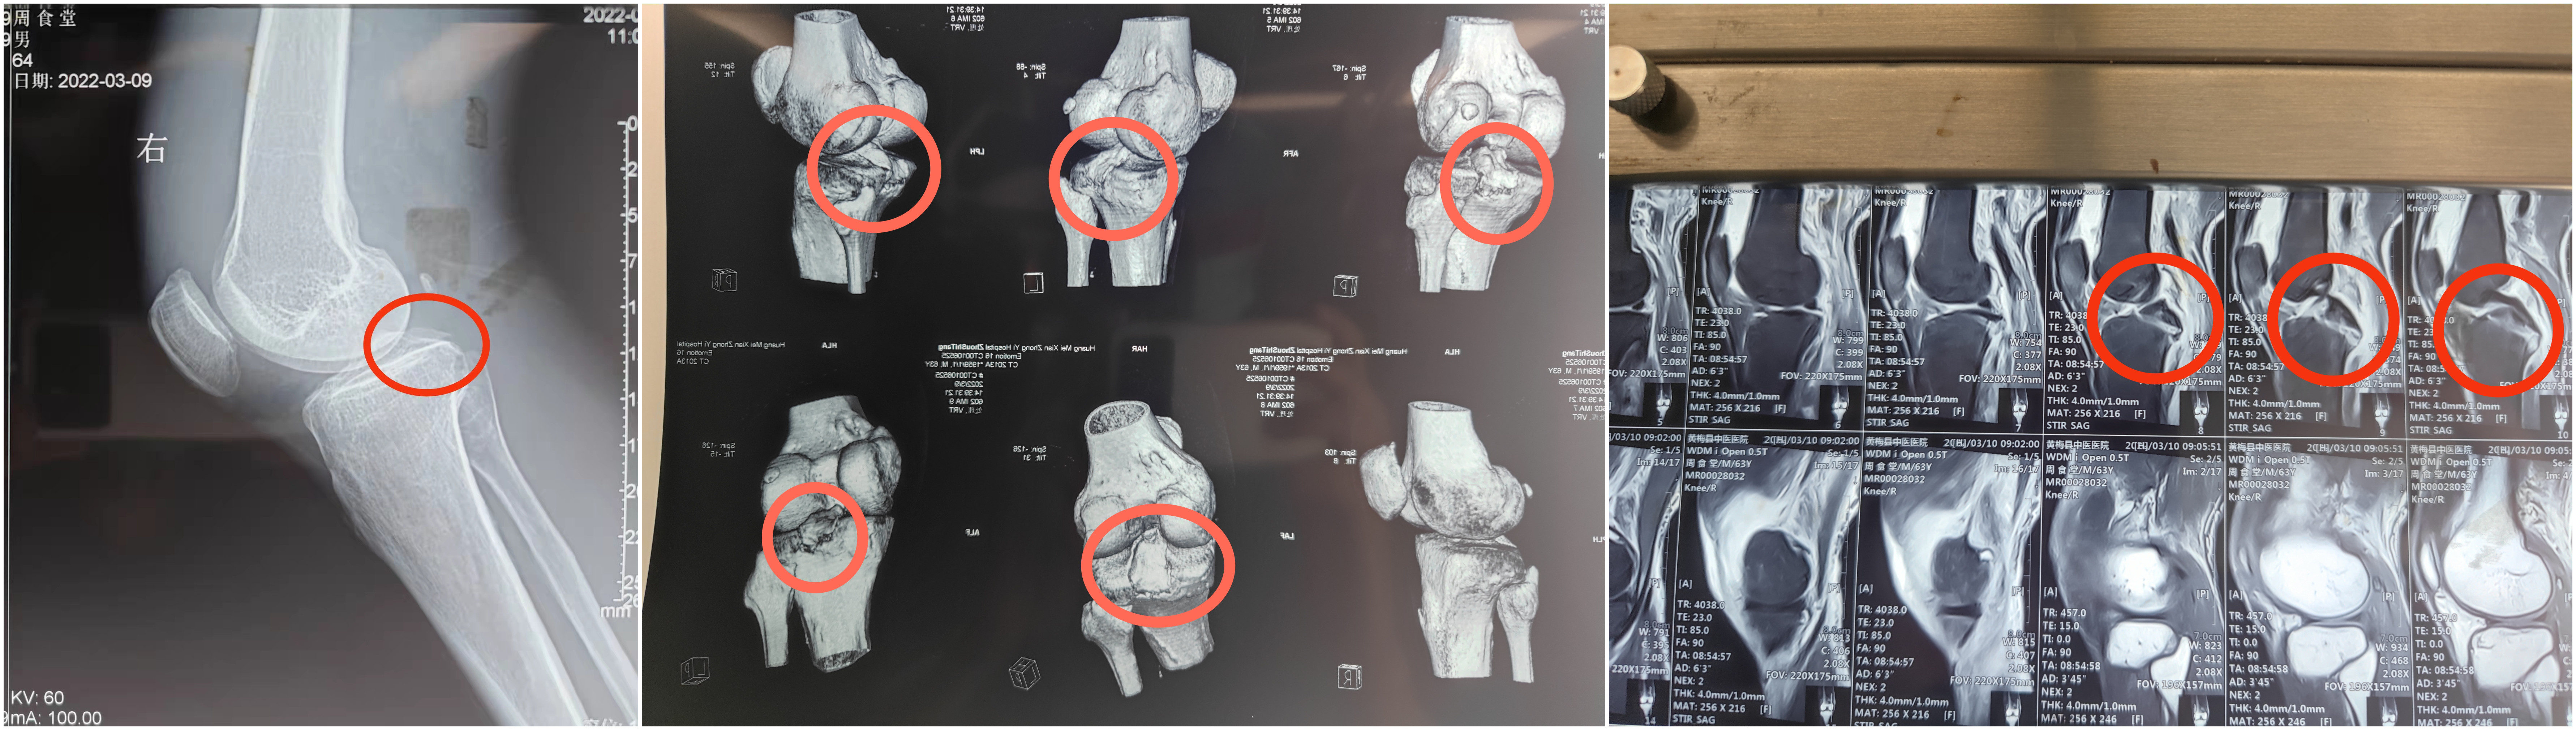

红色圆圈内是后交叉韧带止点附着处骨片,可看见骨片向上翘起